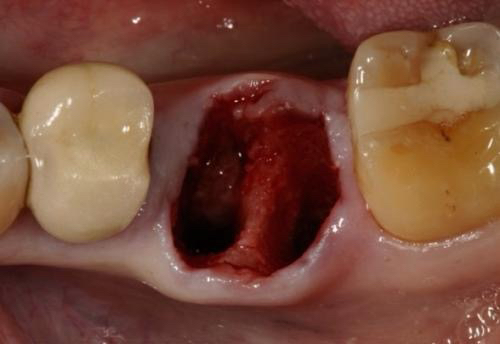

当我们拔牙后会形成拔牙窝洞,半小時後到24小时内会形成一个血凝块宛如嫩豆腐鸭血一样很容易被破坏,血凝块是保护伤口的,也是加速拔牙创伤愈合的。

三、拔牙后血凝块脱落牙槽骨暴露,呈现出干燥表面没有血凝块的天然屏障,因为口腔内不是一个无菌的环境,使得拔牙窝洞暴露于充满细菌的口腔中,而发生骨壁感染形成的干槽症,各位拔牙的宝宝们要注意啦️,会有哪些表现呢?